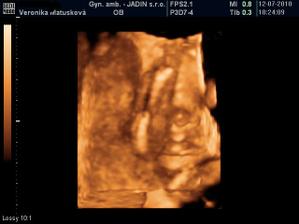

Adamko - 3D/4D

No tot vidno, že je náš syn, sa hanbil a hanbil až sa ukazovať nechcel....ale niekedy sa to podarilo, aj ked to nie je nejaká sláva. Pán doktor nám potvrdil chlapčeka, tak sme radi, vajká ukazoval ako len vedel len toho pipíka stále schovával. Ale je to za nami, pán doktor nás pekne popísal čo je kde, poodmeral nás a povedal, že je všetko v poriadku.